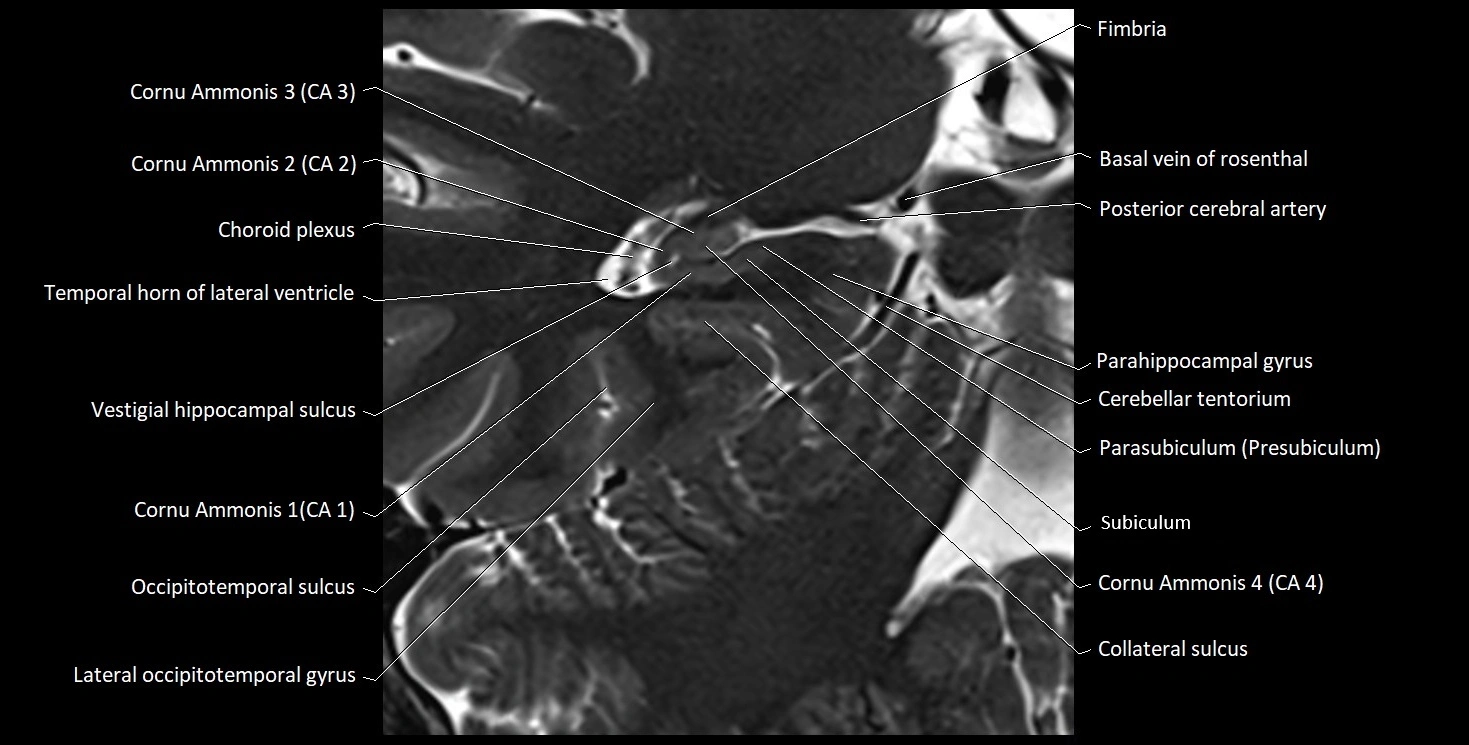

MRI Appearance

T1-weighted images:

• Alveus: Thin linear high signal band (due to myelinated fibers) overlying the hippocampal gray matter.

• Hippocampal gray matter: Intermediate signal intensity.

• CSF of lateral ventricle: Dark (low signal).

T2-weighted images:

• Alveus: Low signal line overlying brighter hippocampal gray matter.

• CSF: Bright hyperintense.